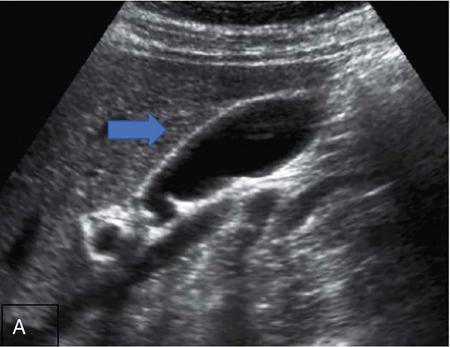

Gallbladder

Normal anatomy

CROSS SECTIONAL ANATOMY OF ABDOMEN Satya Jha NORMAL ANATOMY OF ABDOMEN AND PELVIS Amandeep Singh The two major surfaces: The anterior and posterior layers of the coronary ligament converge on bare area (not covered by peritoneum). Its right and left margins form the right and left triangular ligaments. The right triangular ligament extends toward the diaphragm and separates right subphrenic space from right subhepatic space. The left triangular ligament gives tracts extending to the diaphragm and falciform ligament and does not compartmentalize the left subphrenic space. Ligamentum teres or the obliterated umblical vein is contained in falciform ligament which attaches the liver to anterior abdominal wall. The main portal vein, the proper hepatic artery and the common bile duct are contained within investing peritoneal folds of hepatoduodenal ligament at the porta hepatis (Fig. 7.2.2.1). Liver is divided into eight segments which are functionally independent and have their own vascular supply and biliary drainage. Arterial circulation: The branches of the hepatic artery accompanying the portal veins. Hepatic venous system: The right, middle, and left hepatic veins draining into IVC (Figs. 7.2.2.2 and 7.2.2.3). The gallbladder is a blind pear-shaped muscular membranous sac which is an embryologic derivative of the foregut, is a pouch lying along the undersurface of the liver. The gallbladder fossa is located in the plane of the interlobar fissure, which lies between the right and left hepatic lobes. Its major function is to store and concentrate bile which is produced by the liver. It measures approximately 4 cm in diameter when it is normally distended. Gallbladder is a smaller tubular structure in contracted state. The normal gallbladder wall thickness ranges from 1 to 3 mm. The gallbladder is divided into the fundus, body and neck. Infundibulum is present in the region of neck of the gallbladder, which is called the Hartmann pouch, where gallstones are usually impacted. Intrahepatic biliary radicles (IHBRs) scattered throughout the liver get confluent towards the hilum. They unite to form the right and left main hepatic ducts which further unite to form common hepatic duct (CHD) at the hilum. Common bile duct is formed by the union of cystic duct with common hepatic duct. The main pancreatic duct is joined with the common bile duct to form the ampulla of Vater at the major duodenal papilla (Figs. 7.2.2.4 and 7.2.2.5). Pancreas is located in anterior pararenal space of retroperitoneum anterior to perirenal (Gerota’s) fascia and posterior to parietal peritoneum. It is divided into head, uncinate process, neck, body and tail from right to left. Pancreas lies anterior to portal vein, which marks the point of transition between the body and neck. The region between head of pancreas and second and third parts of duodenum is known as the pancreatic groove. In postnephrectomy cases or with agenesis of kidney or ectopic kidney, pancreas moves posteriorly to partially fill in the empty renal fossa; its soft tissue density should not be mistaken for recurrent tumour. It is located in the pancreatic groove and is bounded superiorly by the duodenal bulb, laterally by second portion of duodenum, inferiorly by third portion of duodenum, medially by superior mesenteric vein and anterior to inferior vena cava. It is a wedge or wedge shaped lying posterior to superior mesenteric artery and vein. It is an imaginary junction between the head and body and lies directly over the junction of the splenic vein and superior mesenteric vein. It is located posterior to the lesser sac and anterior to the aorta, left adrenal gland, left kidney, and renal vessels and runs obliquely upward to the left of the superior mesenteric vessels. It is situated median to the colonic flexure and anterior to the left kidney. It is located in close proximity to the splenic hilum without a notable relation with the body of pancreas. It is seen anterior to the left kidney and median to the colonic flexure. The distal part of the tail passes between the peritoneal layers of the splenorenal ligament (Fig. 7.2.2.6 and 7.2.2.7).